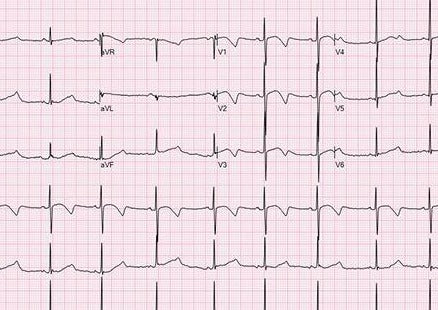

Diagnostic et gestion des arythmies cardiaques les plus courantes des chiens et des chats